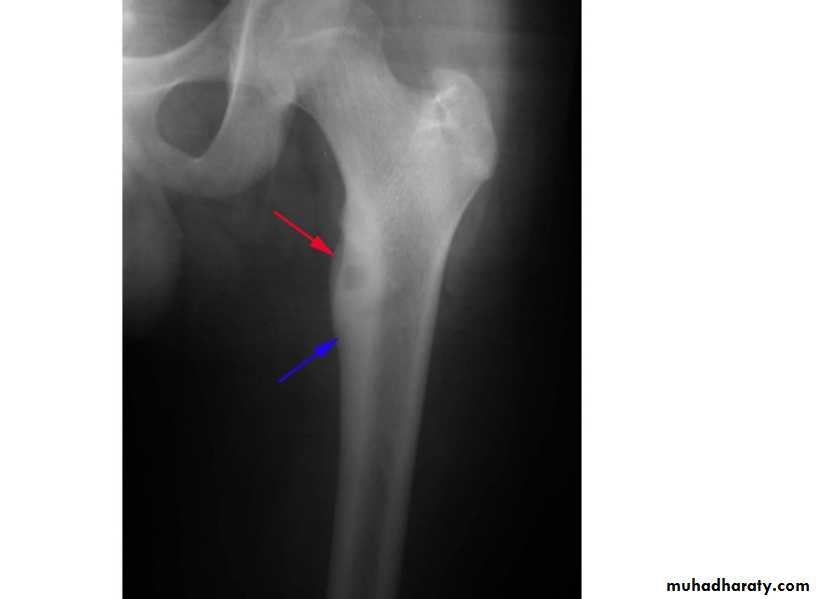

Mushroom Deformity of the femoral neck in perthes disease

being flattened femoral head with a contiguous broad neck, accompanied by awidened articular space .Fallen fragment sign

shepherd crook deformity seen in fibrous dysplasia

A shepherd crook deformity refers to a coxa varus angulation of the proximal femur, classically seen in femoral involvement by fibrous dysplasia .The whole vertebral body marked by vertical striation … being Haemangioma

A shepherd crook deformity refers to a coxa varus angulation of the proximal femur, classically seen in femoral involvement by fibrous dysplasia